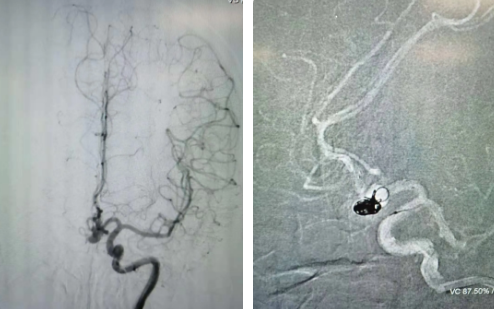

經(jīng)過全面仔細評估,西安國際醫(yī)學中心醫(yī)院神經(jīng)外科陸丹醫(yī)生決定采用微創(chuàng)介入進行治療。在取得患者及家屬同意后,3月11日,陸丹醫(yī)生為患者行Atlas支架輔助顱內(nèi)動脈瘤栓塞術(shù)。

腦血管較外周血管更為脆弱、迂曲,對術(shù)者的操作技術(shù)及精準性要求特別高。術(shù)中,陸丹醫(yī)生通過股動脈穿刺、置入微導管,再通過微導管將彈簧圏送入動脈瘤腔內(nèi),利用彈簧圈的機械閉塞作用,達到防止動脈瘤破裂的目的。術(shù)后,患者各項生命體征平穩(wěn)。

陸丹醫(yī)生介紹,此次腦科醫(yī)院首次采用Atlas支架輔助進行顱內(nèi)動脈瘤栓塞術(shù)。以往動脈瘤栓塞術(shù)中的支架輸送導管較粗,支架順應性差,易使載瘤動脈移位,而Atlas支架的輸送導管很細,輸送順滑,同時順應性及貼壁性強,能夠適應迂曲的腦遠端血管。